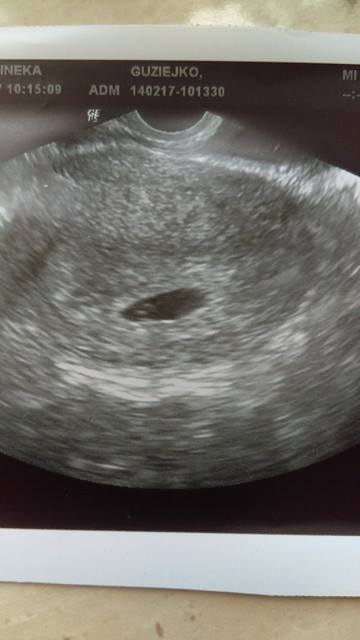

A tutaj chcę się pochwalić USG, no i ja jakoś widzę dwie kropki a nie jedną. Co o tym myślicie?

A tutaj chcę się pochwalić USG, no i ja jakoś widzę dwie kropki a nie jedną. Co o tym myślicie? Zobacz załącznik 795438

Gratuluje!!!! Masz dwa kropki [emoji255][emoji259]

Ja też widzę dwie. Który to tydzień?

Licząć od pierwszego dnia ostatniej miesiączki to będzie 7, ale ja miałam wszystko popieprzone i owulację miałam 18 stycznia dopiero. Także może to jest jakiś 5-6 tydzień, z tego wszystkiego nawet nie zapytałam ginekologa. 20 lutego jadę prywatnie to tam już wszystkiego się konkretnie dowiem.

To zapewne dzidzia i pęcherzyk żółtkowy [emoji4]